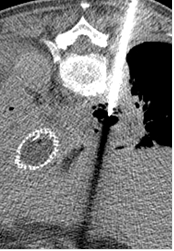

Cas 2 : Pseudo-anévrysme sur branche sous-segmentaire de l’artère pulmonaire droite

après multiples drainages pour infection pleuro-pulmonaire sévère. Contrôle avant et après

embolisation par coil.